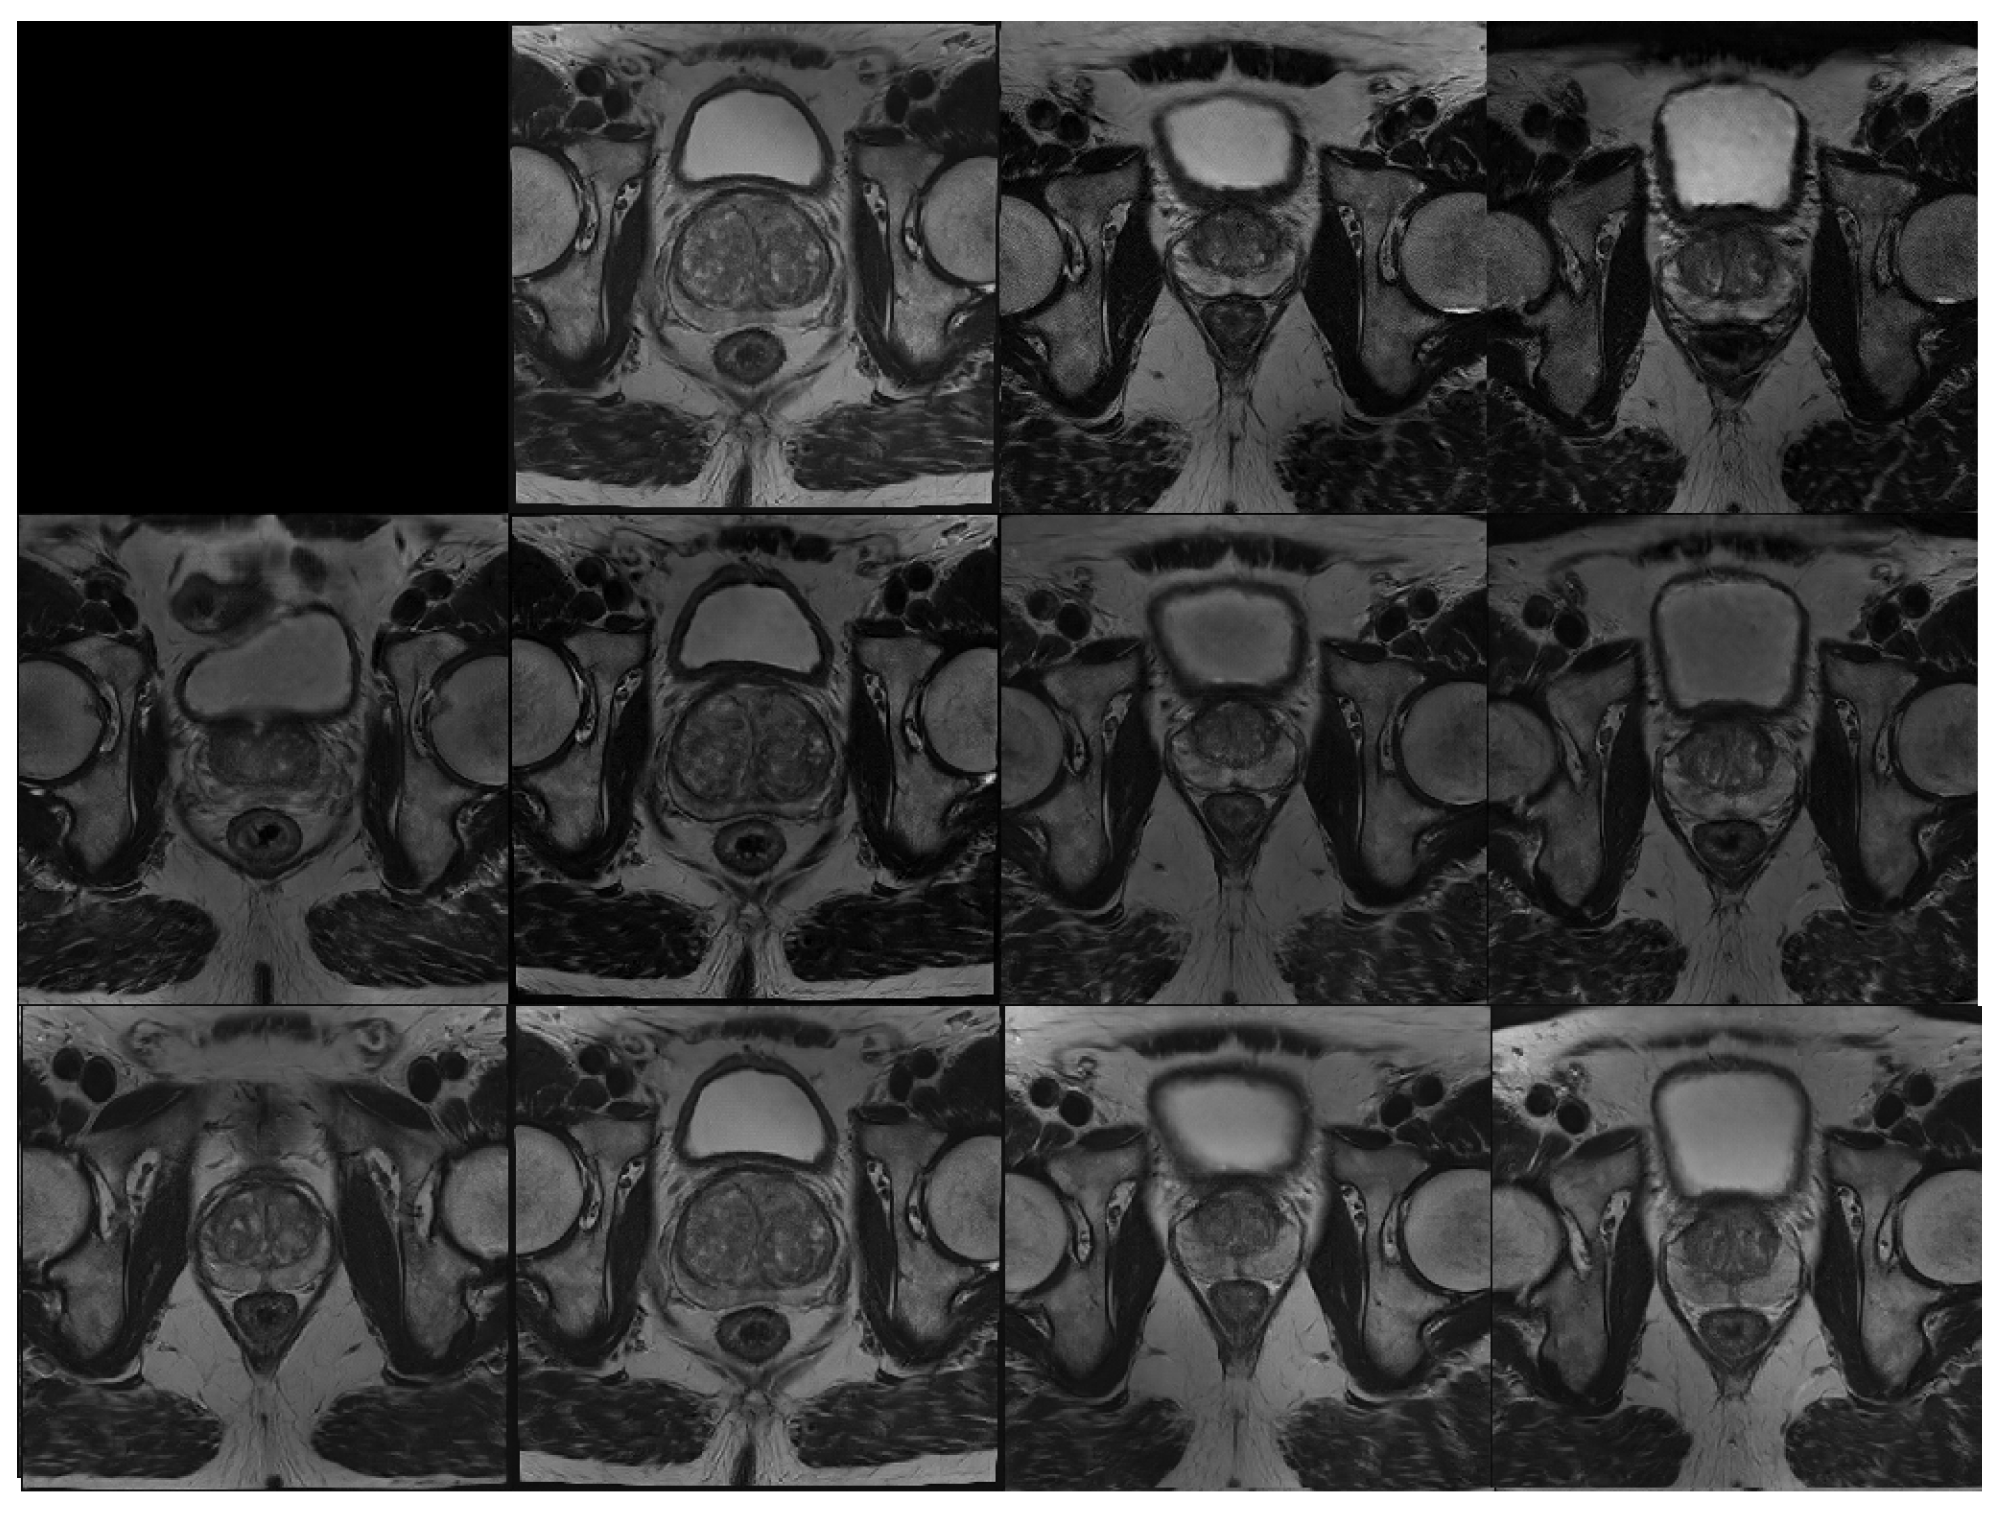

Figure A2 shows the result of style mixing applied using the High-Res model. Each cell in the grid combines style vectors from two independently sampled latent codes. The first row and first column contain reference images generated without mixing. For the remaining cells, coarse (low-resolution) styles are taken from the column latent code, while fine (high-resolution) styles are taken from the row latent. This enables controlled recombination of structural and appearance features.

The results illustrate the model’s capacity to disentangle anatomical layout from intensity-based appearance. Images in the same column retain consistent spatial structures, such as prostate and bladder shape, determined by the coarse styles of the column latent. In contrast, images across rows vary in intensity and contrast, reflecting the fine styles of the row latent. These findings indicate that the High-Res model supports independent control over structural and visual attributes, reinforcing its suitability for controlled medical image synthesis.

Figure A2. Style mixing example. Middle slices from synthetic volumes are shown. The first row and first column correspond to images generated from independent latent codes. Each remaining image combines anatomical structure from the column source (coarse styles) with intensity and contrast features from the row source (fine styles), demonstrating disentangled control over structure and appearance.